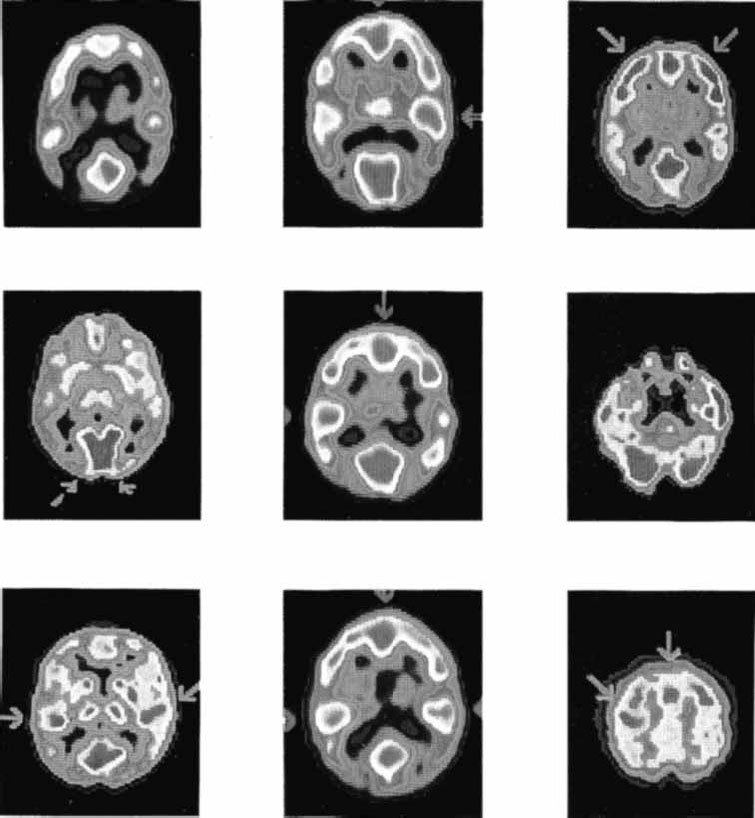

Рис. 2.16. Результаты ПЭТ сканирования мозга здорового человека в различных экспериментальных ситуациях (Phelps, Mazziotta, 1985).

Этот метод позволяет оценить метаболическую активность в различных участках мозга. Он во многом схож с авторадиографией: испытуемый проглатывает радиоактивное соединение, позволяющее проследить изменения кровотока в том или ином отделе мозга, что косвенно указывает на уровень метаболической активности в нем. Таким радиоактивным соединением может быть 2-дезоксиглюкоза, имеющая одну из меток – радиоактивные изотопы углерода (С11), фтора (F18), кислорода (О15), азота (N13).

Время полураспада этих веществ составляет от 110 сек для фтора до 120 сек для кислорода. Метаболически активные участки мозга с большей интенсивностью поглощают 2-дезоксиглюкозу из крови, которая в отличие от обычной глюкозы не включается в метаболические процессы и только накапливается в мозге. Радиоактивные изотопы излучают позитроны, которые, встречая в мозге электроны, уничтожаются (аннигилируют), излучая 2 гамма-луча, направляющиеся в противоположные стороны. В специальной камере монтируются детекторы гамма-лучей, собранные в кольца. В камеру помещается голова испытуемого, радиоактивные молекулы 2-дезоксиглюкозы фиксируются сканером (Plum e. a., 1976) (рис. 2.16). Полученные данные обрабатываются компьютером, и на основе результатов воссоздается картина метаболически активных участков мозга.

Особенностью ПЭТ является то, что она позволяет снимать «динамические» картины функционирования мозга, решающего ту или иную задачу или пребывающего во сне. Использование кислорода позволяет получать характеристики регионального кровотока, объема крови, потребления кислорода. Однако и кислород, и глюкоза попадают в мозг с током крови, изменение которого происходит иногда в течение нескольких минут. Поэтому быстропротекающие процессы пока этим методом фиксировать не удается.